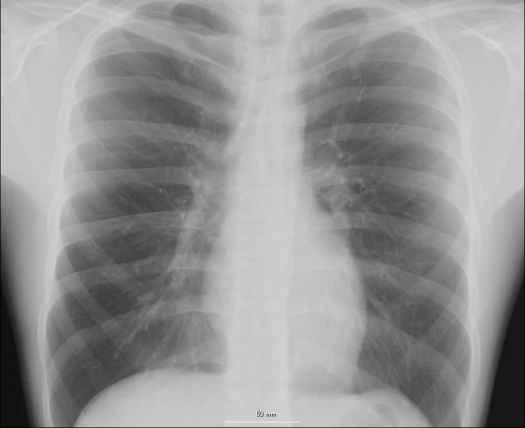

幾週前,我們發現了一個演化實例:細胞層面的演化,而且是在人類體內發生的演化。一項針對心臟科醫師的小型研究發現,這些醫生血液中的過氧化氫含量高於正常水平。心臟科醫師在工作中經常使用X光,而這項發現可能預示著未來可能接觸到致癌物質。但研究也發現,過氧化氫水平的升高會觸發一種名為穀胱甘肽的抗氧化劑的產生,而穀胱甘肽是一種細胞保護劑。本質上,這些醫生正在從內而外地增強自身抵禦職業危害的能力,而這種保護機制始於細胞深處。這是一個令人驚嘆的故事——點擊此處了解更多詳情。